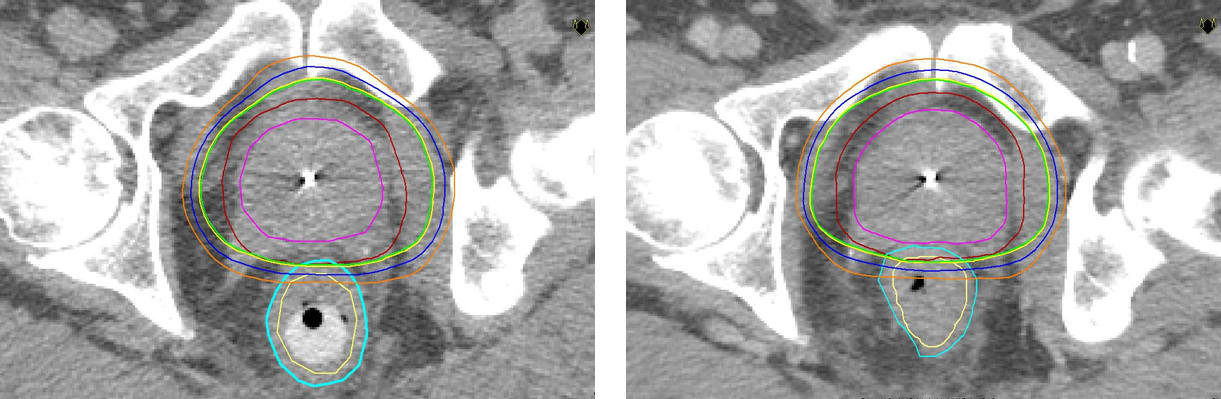

2005 var Akademiska pionjär i Sverige med strålbehandling med rektalstav mot prostatacancer. Sjukhuset är fortfarande ensamt om att erbjuda denna form av strålbehandling som ger färre biverkningar än andra jämförbara metoder. Metoden gör det möjligt att ge högre dos i prostata och skona frisk vävnad/intilliggande organ.

– Precis som vid annan strålterapi är målet med stavbehandling att döda cancercellerna. Vi behandlar 25-30 patienter per år med denna metod. Fördelen är att man kan öka avståndet mellan prostata och ändtarmen och därigenom ge högre stråldos i prostata och lägre i ändtarmen så att frisk vävnad skonas. Jämfört med konventionell strålbehandling utan rektalstav, som är vanligast idag, kan man ge lite högre stråldos utan fler biverkningar, säger Kristina Nilsson, överläkare i onkologi vid Akademiska sjukhuset.

Strålning är ett vanligt sätt att behandla prostatacancer, både när cancern är kvar i prostatan och när den spridit sig till andra delar av kroppen. Vid tidig sjukdom, när tumören inte spridit sig utanför prostatakörteln, är strålning ett likvärdigt alternativ till kirurgi som botande behandling. Forskning har visat att ju högre stråldoser man kan ge tumören, desto större är chansen till bot. De doser som fortfarande användes för något decennium sedan var ofta inte tillräckligt höga för att bota patienten. Det finns nu en stark strävan att utveckla metoder som gör att man kan öka stråldosen utan att förvärra biverkningarna.

En utmaning vid prostatacancer är precisionen eftersom prostatakörteln är rörlig, men strålningstekniken har successivt blivit allt mer träffsäker. Man skiljer på yttre strålning (strålkällan är utanför patientens kropp) som t ex strålbehandling med rektalstav, eller olika typer av intern strålbehandling, så kallad brachyterapi.

* Rektalstaven förs in i ändtarmen som trycks nedåt och separeras från prostatan. På så sätt kan stråldosen minskas till ändtarmen.